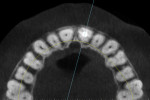

When a tooth is fractured or requires extraction, a dental implant is the only treatment option that will restore the root of the tooth, which can provide support for a new clinical crown. A CBCT scan can provide an accurate 3D-reconstructed volume as an aid in planning for an implant-supported restoration (Figure 1). The cross-sectional image reveals the precise location of the root within the alveolus, provides information on bone density, and shows that the tooth had previous root canal therapy (Figure 2). The axial image is important to help determine the morphology of the tooth root based upon the inferior-superior location of the slice (Figure 3). Depending on the interactive treatment planning software, the use of realistic manufacturer-specific virtual implants of known length and diameter can be simulated within the receptor site (Figure 4). The yellow projection is a helpful tool to aid the clinician in establishing the proper trajectory of the implant within the cross-sectional image and in relation to the desired restorative option (ie, screw- or cement-retained). It should be noted that this is only one slice, and that the final positioning of the implant should be determined only after all views have been considered.